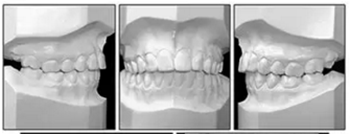

6年后治療結(jié)果保持穩(wěn)定(圖11,圖12 ; 圖13)??梢杂^察到穩(wěn)定的間隙關(guān)閉,正常的覆蓋和覆合,上下牙中線一致,微笑美觀。建議完美替代了拔除的側(cè)切牙。正畸治療后進行牙齒美白。